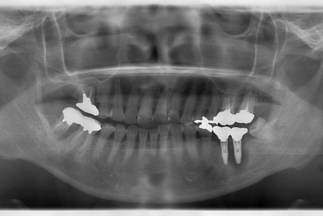

- Before

| 治療内容 | 上顎2本、下顎2本のインプラント治療による咬合再構成 |

| リスクについて | 解剖学的リスク:上顎洞穿孔、下顎管損傷など |